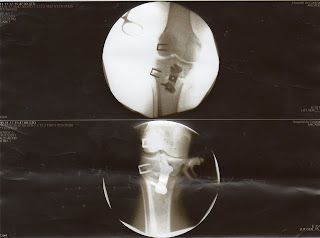

.:. Esse é o meu "novo" joelho .:.

Conheça meu "novo" joelho depois da cirurgia, ficou bonitinho não? Será ainda consigo entrar em algum Banco sem ser barrado na porta que tem detector de metais?

Não se assuste com aquela tesoura que aparece no RX... esse RX foi tirado no momento da cirurgia, ou seja, antes de me costurarem...